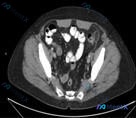

这是一份盆腔水平的腹盆腔CT横断面(软组织窗)报告:

- 肠管及管腔:盆腔内多个小肠肠管断面,管腔内见气体及液性内容物;肠壁结构连续,未见明显增厚或局限性肿块;肠周脂肪间隙清晰,未见明显渗出、条索或积液。

- 腹膜及盆腔:未见明显游离腹水;腹膜后及盆腔未见明确肿大淋巴结;盆腔脏器(如膀胱)形态未见明显异常。

- 血管、软组织及骨骼:腹壁层次分明,未见疝或软组织肿块;骨盆、股骨头等骨骼结构完整,未见骨质破坏;盆腔大血管走行正常。

- 原始总结:本层面主要显示盆腔小肠肠管,管腔及周围软组织结构未见明显占位、炎性改变或异常积液;骨骼未见明显异常。